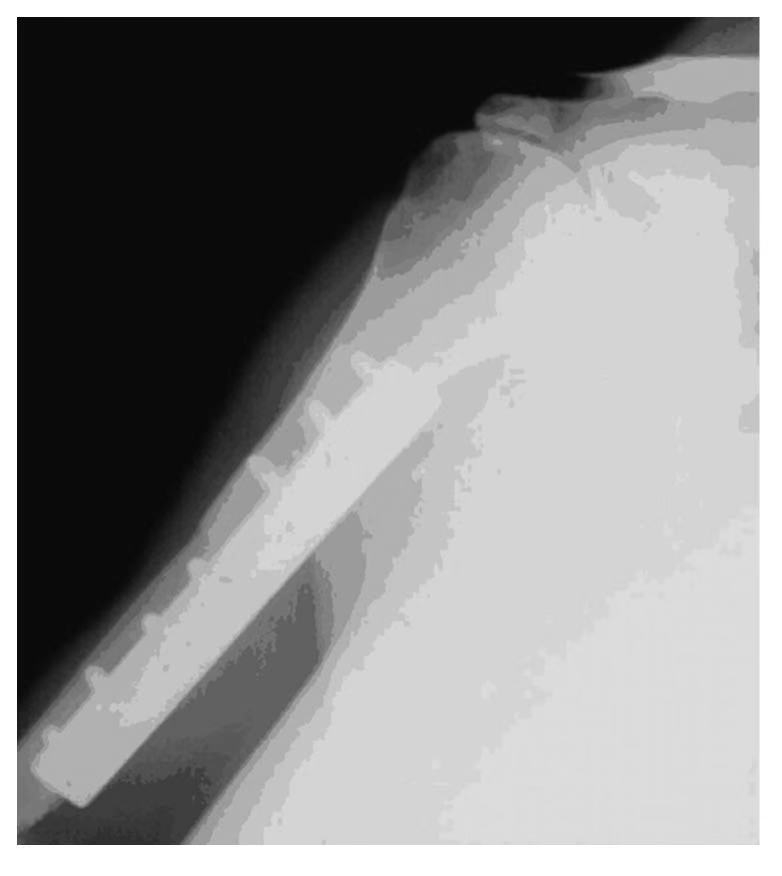

对于大段的骨关节缺损如肿瘤切除后造成的骨缺损,临床处理很困难。采用自体骨可造成供骨部位的功能丧失,而且体内可供的自体骨来源有限。各种生物替代材料如金属假体虽然可供利用,但其存在远期松动、磨损等一系列问题,难以满足重建肢体功能的要求;同种异体骨关节置换是较为理想的方法(图4-0-3、图4-0-4)。

图4-0-3 取下的同种异体肱骨

图4-0-4 肱骨肿瘤切除的同种异体骨关节移植术后X线片